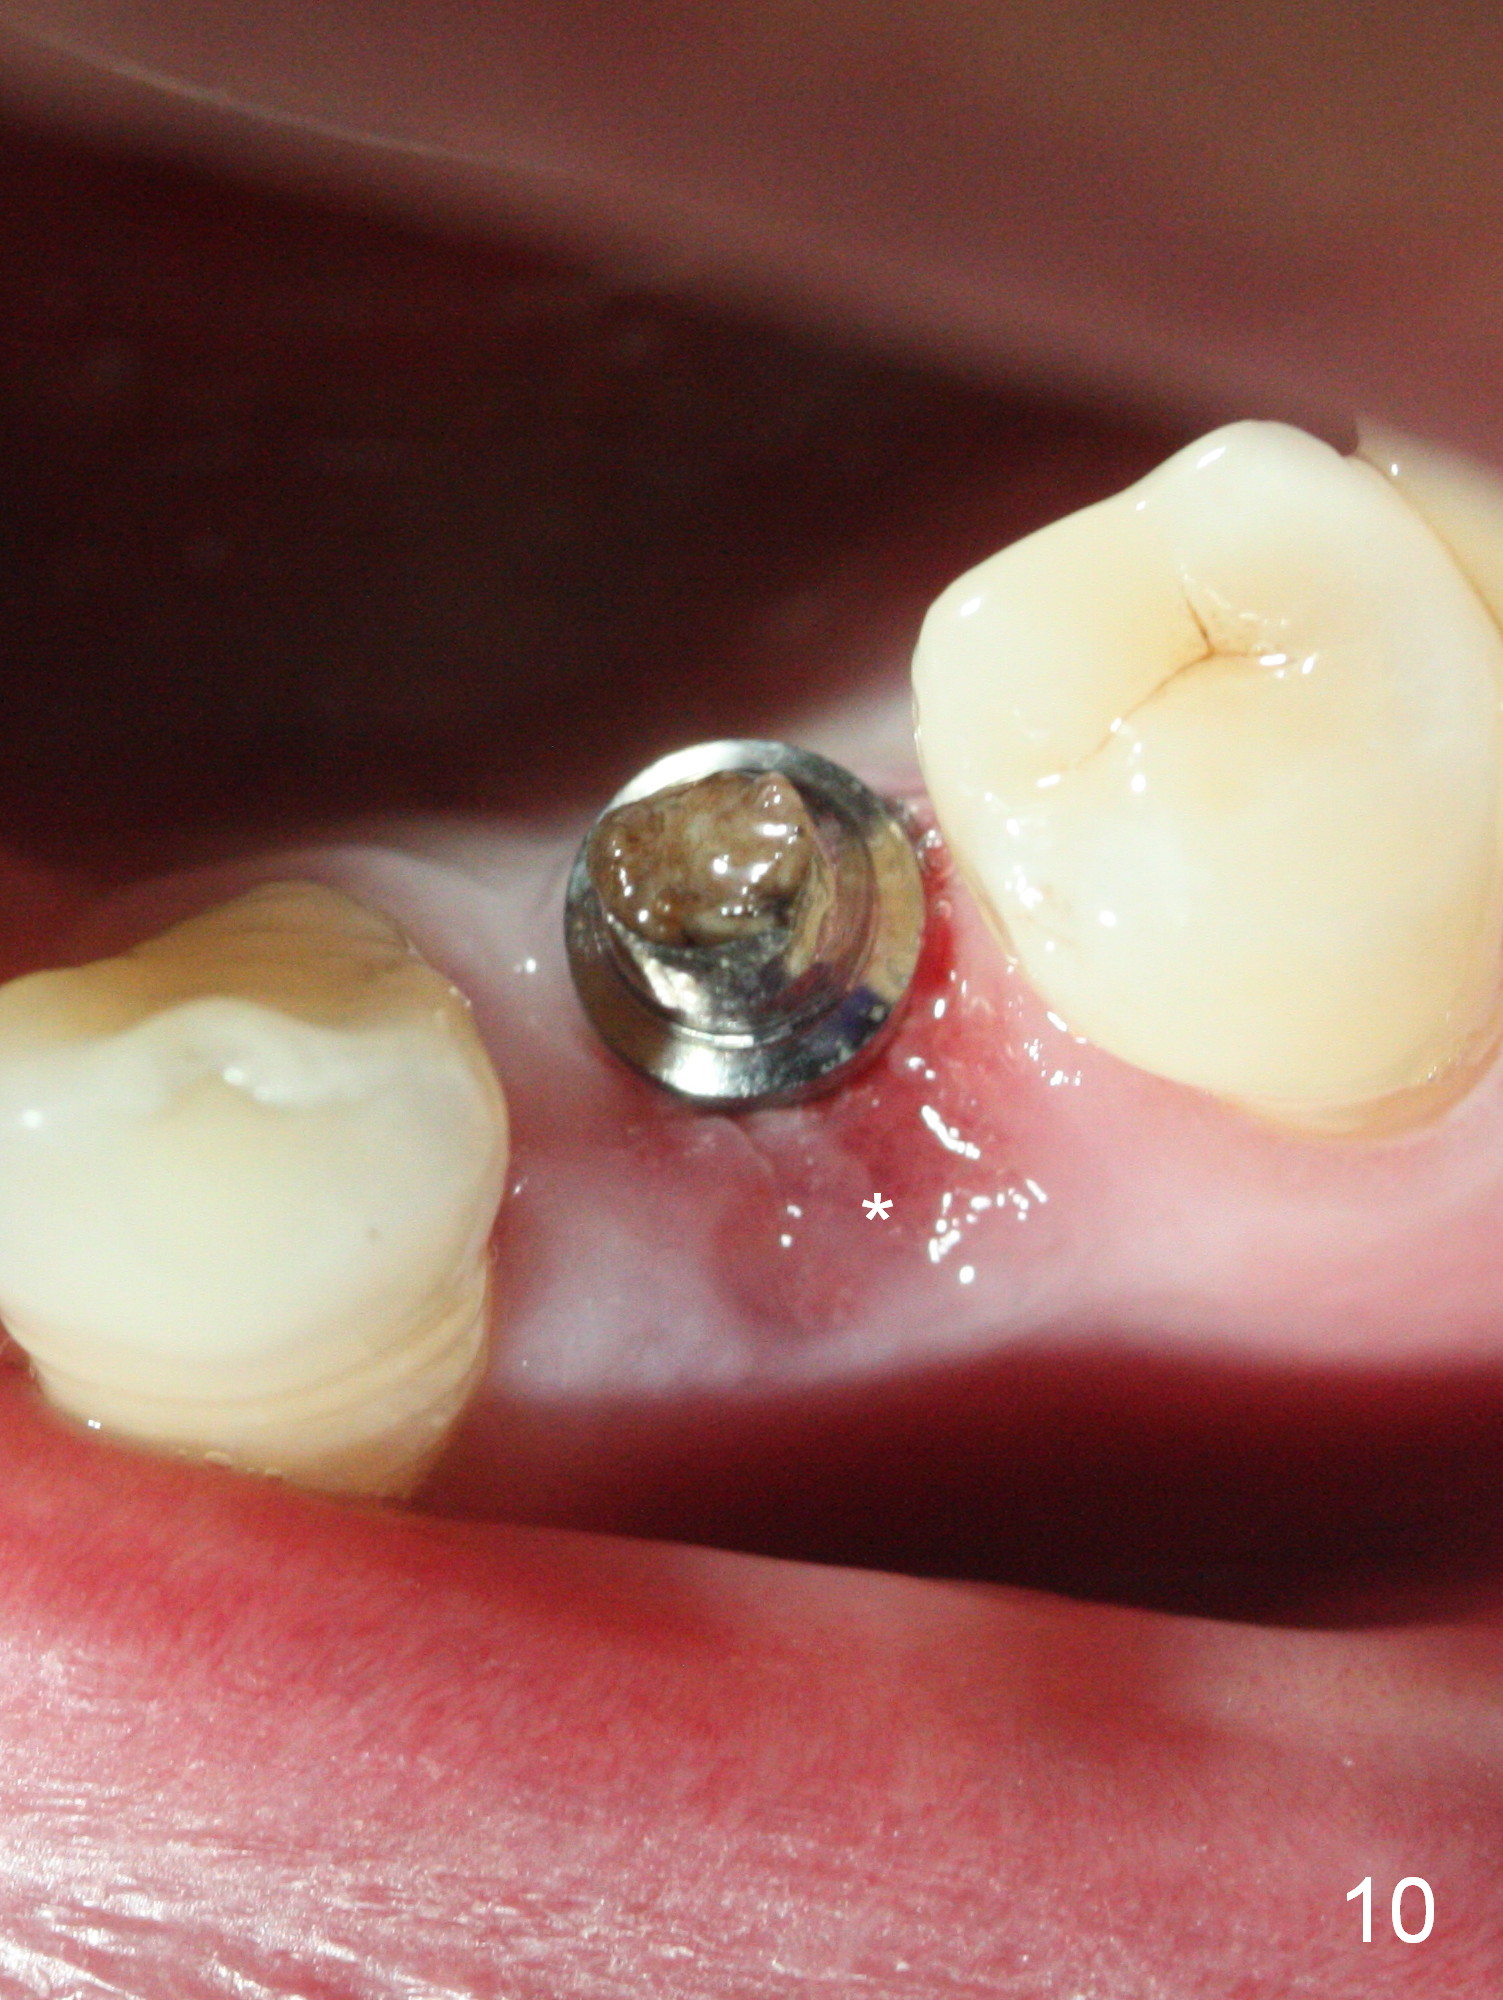

The implant seems to have osteointegrated 4 months postop (Fig.9).  When a permanent crown is fabricated, it should have normal occlusal and buccal contour (from Fig.11 (provisional) to 12 red and black curved lines) as well as the buccal cervical extension (Fig.12 to cover the buccal gingiva (Fig.10 *).  If the lingual margin of the abutment is too prominent, return the case and the abutment will be changed to the one with 2 mm cuff (existing 3 mm).  The lingual margin of the abutment will be trimmed.  The patient is not pleased with the short buccal margin of the crown after cementation (Fig.13).  In fact the provisional should have been fabricated so that the its buccal margin should be subgingival and within the gingival outline.  It may prevent buccal plate collapse.  In fact the crown dislodges 1 year post cementation.  The lingual margin is prep lower to increase the abutment height.  Impression is taken.  Although the access hole is unnecessary for cementation, it acts as an escape hole so that there is no excess cement cervically (Fig.14-18).